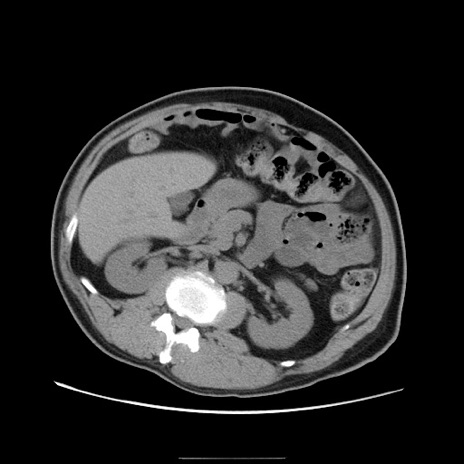

症例22(横断像)

【症例】50歳代男性

【主訴】腹痛

【現病歴】AVMからの被殻出血のため回復期リハ病棟入院中。 本日午後3時頃急に下腹部痛が出現した。

【既往歴】AVM、被殻出血、虫垂炎、高血圧

【身体所見】意識晴明、左半身不全麻痺、会話の理解は良好、36.5°C、腹部:膨隆、全体に板状硬、下腹部正中に圧痛点あり、反跳痛-、筋性防御不明、右下腹部にope scar

【データ】WBC 9400、CRP 0.06